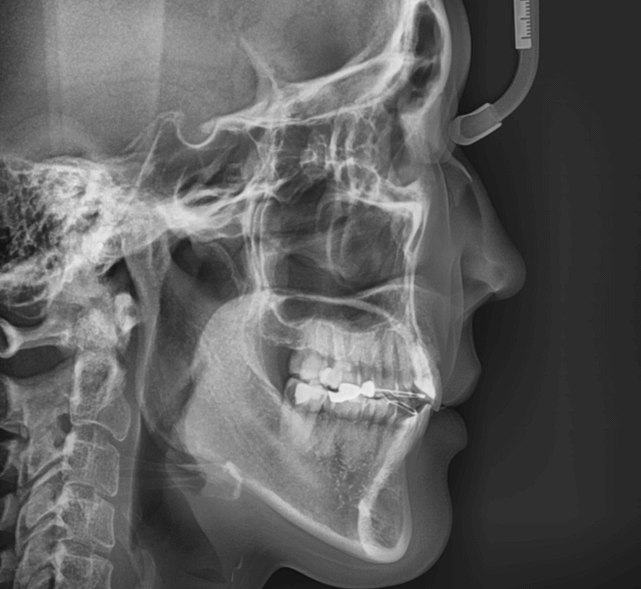

| 年齢・性別 | 34歳の女性 |

|---|---|

| 主訴 | 口元の突出感が気になり、将来的な咬合状態を整える目的で来院された患者様です。 |

| 治療期間・回数 | 3年3ヶ月・31回 |

| 費用 | 830,000円 |